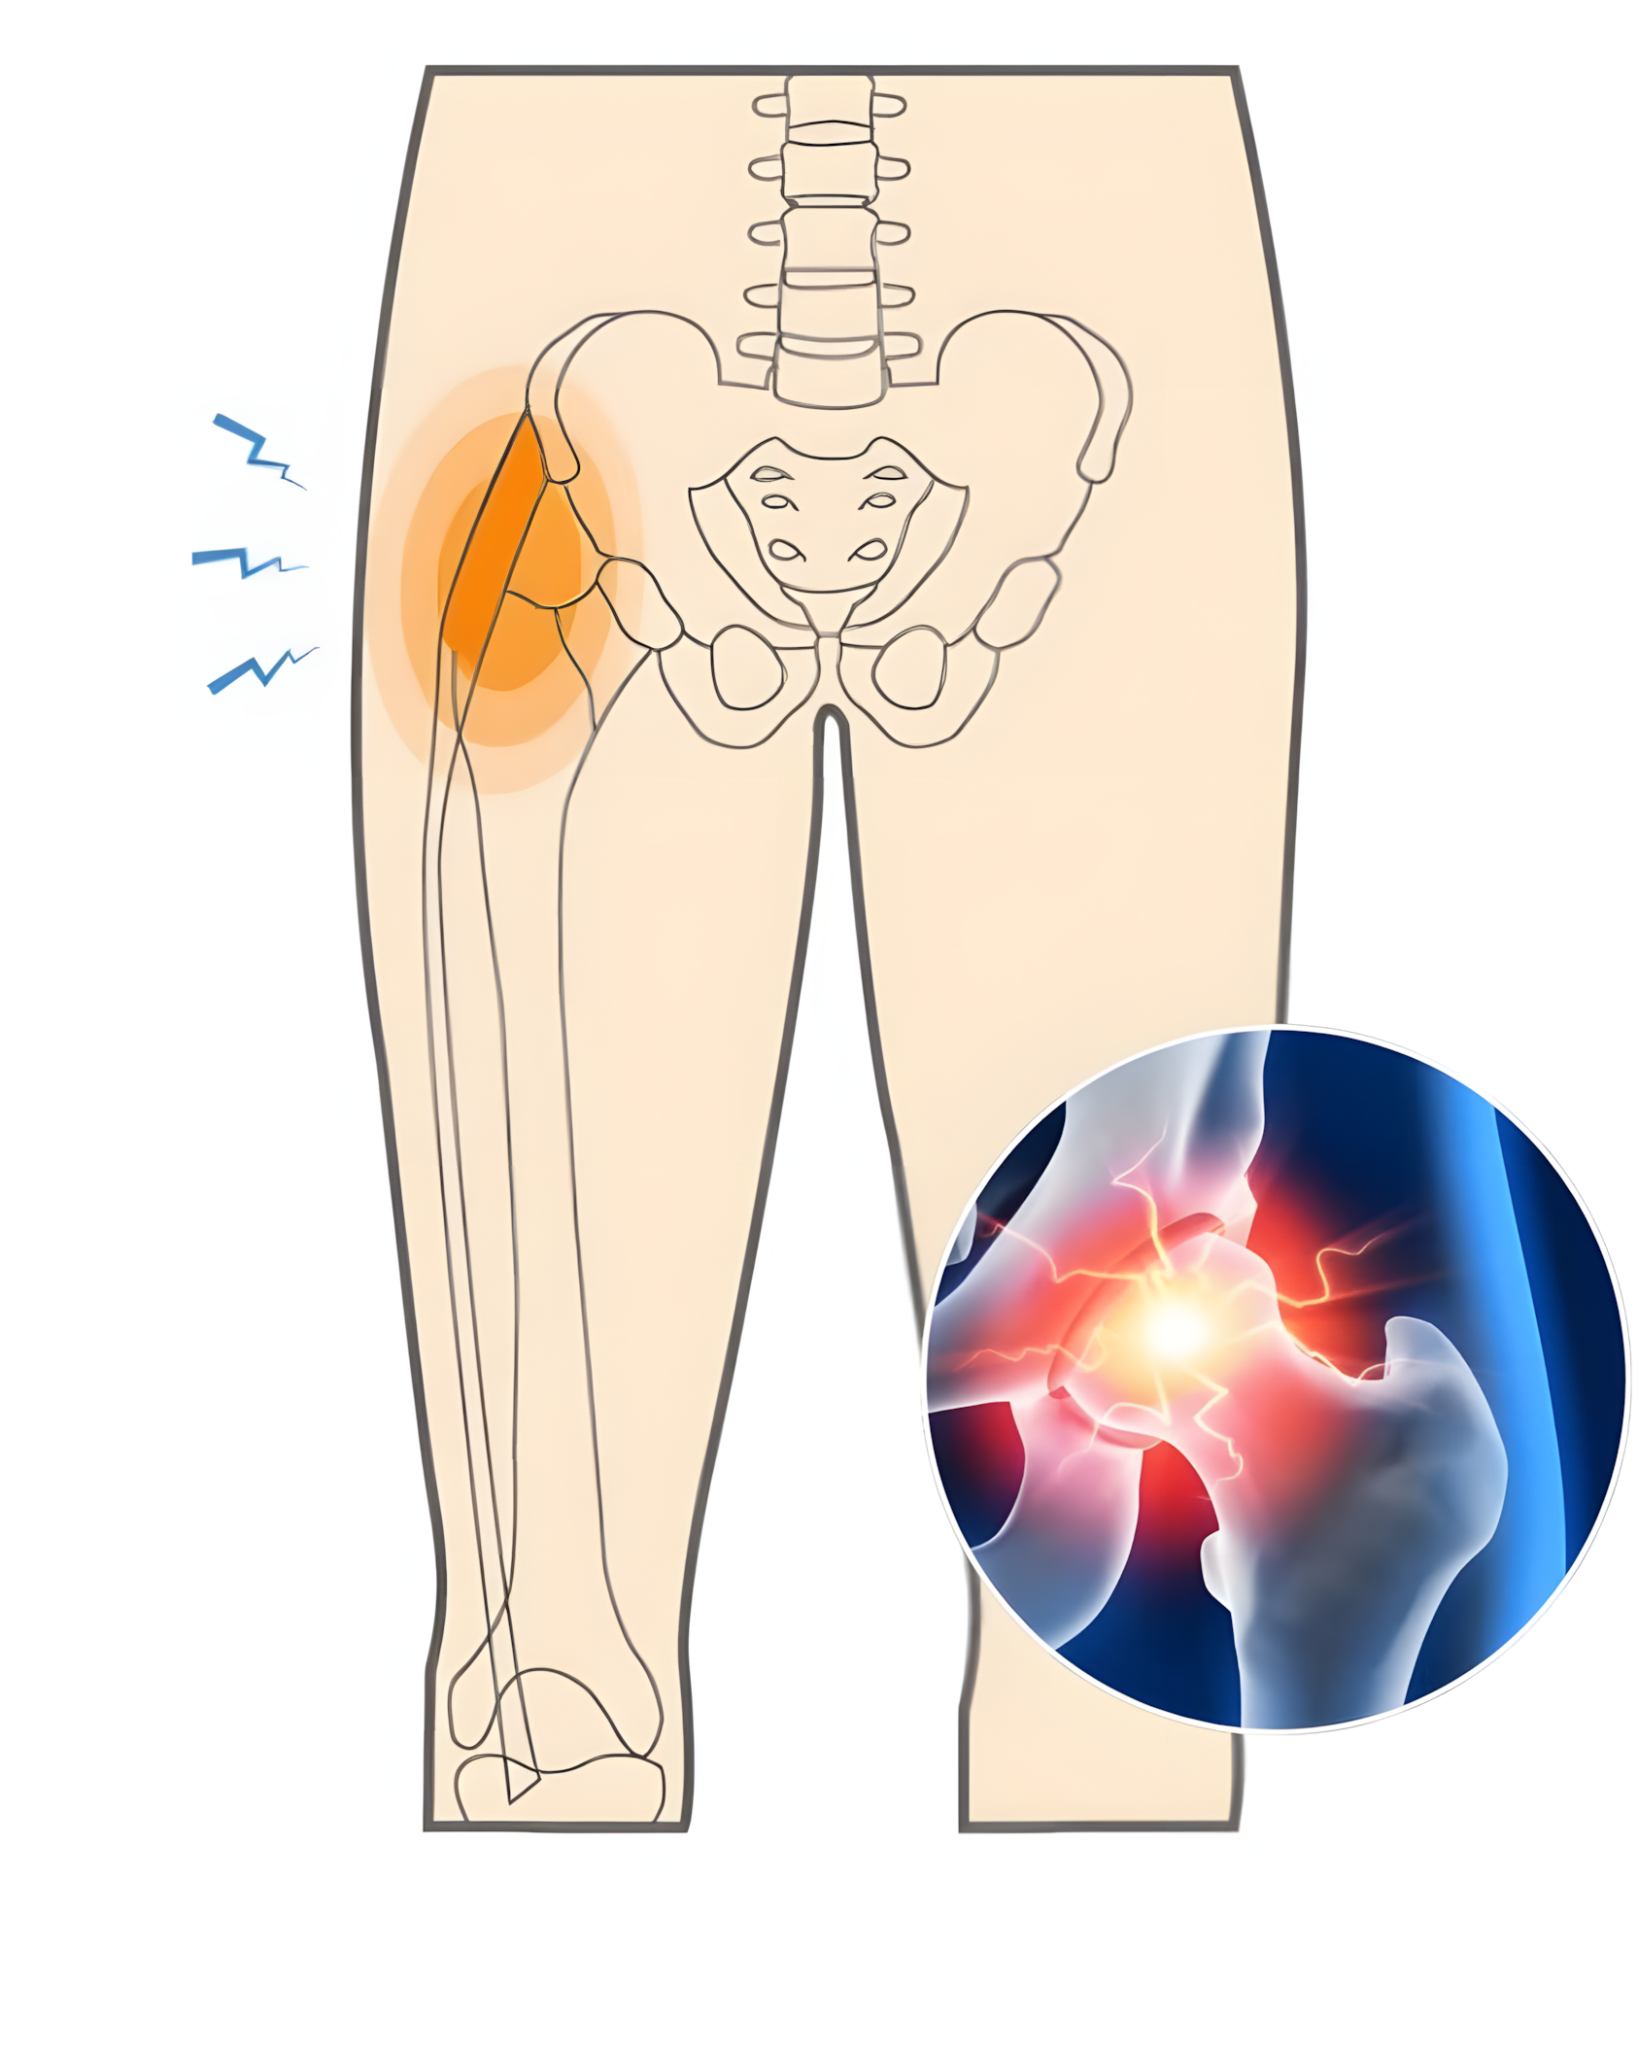

Nu kun je later op sommige van deze dingen klikken, maar je zult zien wat je doet en dan zul je zien wat je doet. Door slijtage van het kraakbeen en het heupgewricht – ook wel artrose genoemd – komt de pijn neeens dichterbij.

Het kraakbeen is normaal als schokdemper, verdwijnt langzaam. Hierdoor zenuwen bloot, en dat voel je. Dan zie je dat de zelfs vallen en de klappen er nog steeds zijn.

Dit verdwijnt vaak na wat beweging, maar keert steeds terug. Houd er rekening mee dat de tijd die u neemt voorbij is, het gewicht is te hoog. Zelfs het slaan van veteranen kan pijnlijk worden. De ongemakken komen voort uit de verminderde demping tussen de flessen.

Sommige mensen merken een krakend of schurend gevoel in de heup, ook er iets verslijt. Dan wil je het woord dunner en ruwer horen. Pijn straalt soms uit naar de leugens, zelfs de knie.

Het voorkomen van de lijtage vordert, neemt de klachten toe. Na een tijdje werd het onstabiel en was het te laat om wakker te worden. Een warme gezwollen heup mogelijk op een steking, wat extra ongemak veroorzaakt.